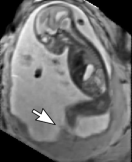

Reconstruction of Fetal Organs: Exemplary PVR and SVR reconstructions under motion introduced by kicking of the fetus are shown in Fig. 11. PVR reconstruction results show an improved visual appearance and less blurring in the region with severe motion artifacts (arrow). An example of a challenging clinical case with a kidney malformation in one of twin fetuses, is shown in Fig. 8. Our clinical partners confirmed that such complications are easier to examine and to quantify after PVR-based reconstruction.

(a) Input

(b) SVR

(c) PVR